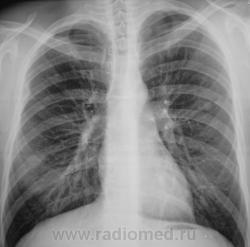

Пол пациента: Мужской пол Тип патологии: Другое Область исследования: Грудная клетка и верхние дыхательные пути Методы исследования: Rg Туберкулома? https://radiomed.ru/sites/default/files/styles/case_slider_image/public/user/12/2.pb240005a.jpg?itok=xfKB85vZ ID:9364 Thu, 25/11/2010 - 01:21 #1 Катенёв Валенти... Offline Last seen: 7 years 3 weeks ago Joined: 22.03.2008 - 22:15 Posts: 54876 Продолжение. [[wysiwyg_imageupload:690:]][[wysiwyg_imageupload:691:]][[wysiwyg_imageupload:692:]][[wysiwyg_imageupload:693:]] Thu, 25/11/2010 - 05:24 #2 Helios Offline Last seen: 7 months 3 weeks ago Joined: 06.08.2010 - 15:16 Posts: 4417 А здесь?Приложения: Thu, 25/11/2010 - 14:34 #3 lupan Offline Last seen: 6 years 10 months ago Joined: 07.01.2010 - 17:17 Posts: 1406 Helios wrote: А здесь? Туберкулома-то имеется. Но не она здесь самая "страшная". Великое преймущество врача заключается в том, что он не обязан следовать собственным советам. ( А. Кристи) Thu, 25/11/2010 - 14:46 #4 Катенёв Валенти... Offline Last seen: 7 years 3 weeks ago Joined: 22.03.2008 - 22:15 Posts: 54876 Наша "туберкулома", конечно, требует д/диагностики с периферическим раком лёгкого. Thu, 25/11/2010 - 21:06 #5 Катенёв Валенти... Offline Last seen: 7 years 3 weeks ago Joined: 22.03.2008 - 22:15 Posts: 54876 Пациент прооперирован в ОПТД, диагноз подтвержден. Снимки ниже.Приложения: Thu, 25/11/2010 - 21:13 #6 Катенёв Валенти... Offline Last seen: 7 years 3 weeks ago Joined: 22.03.2008 - 22:15 Posts: 54876 Фрагменты снимков и томограмма.Приложения:

Туберкулома-то имеется. Но не она здесь самая "страшная".

Наша "туберкулома", конечно, требует д/диагностики с периферическим раком лёгкого.